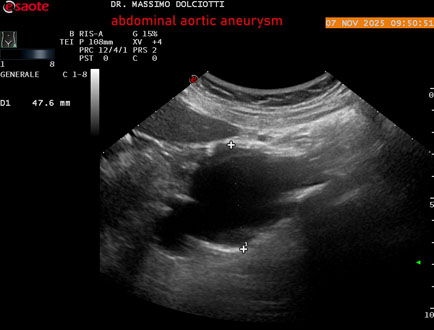

Data inserimento: 11/11/2025

Ecografia del: 07/11/2025

Strumento: Esaote MyLab Eight

Sonda: Convex Multifrequenza 1-8 MHz

Età Paziente: M 60 anni

Motivazione dell'esame: follow up per aneurisma dell'aorta addominale.

Commento all'esame: le immagini ed il video documentano la presenza dell'aneurisma dell'aorta addominale sotto-renale, con diametro antero-posteriore massimo documentato di 47 / 48 mm.

Conclusioni: aneurisma dell'aorta addominale in follow up (abdominal aortic aneurysm follow-up).

Presentazione: Dr. Massimo Dolciotti - Ancona

Elaborazione digitale: Andrea Dini - Ancona